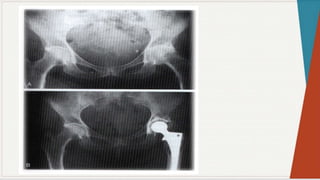

Radiografia Simples:

◗ Incidência ântero-posterior:

observar

as

características: espaços

articulares e

linhas

seguint

es

pélvica

s,

presença de qualquer doença óssea, ângulo colo-

diafisário, forma da cabeça femoral, presença de

osteófitos, evidência de fratura ou luxação,

evidência de deformação pélvica.

Radiografia Simples: ◗ Incidênciaântero-posterior: observar as características: espaços articulares e linhas seguint es pélvica s, presença de qualquer doença óssea, ângulo colo- diafisário, forma da cabeça femoral, presença de osteófitos, evidência de fratura ou luxação, evidência de deformação pélvica.